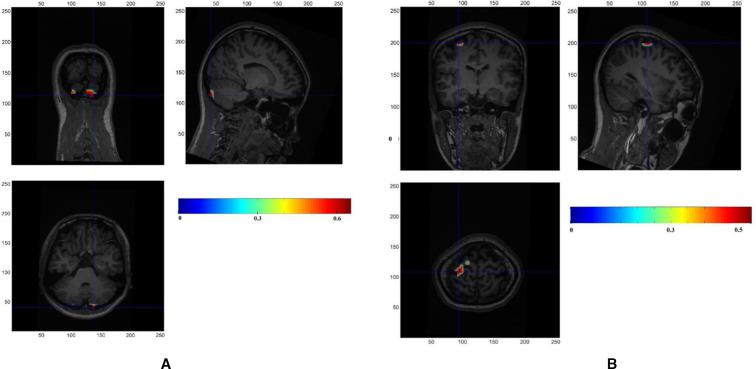

Initially, zolpidem, a non-benzodiazepine hypnotic agent, was considered to have fewer adverse reactions than traditional benzodiazepines. However, after zolpidem was approved for medical use, an increasing number of case reports have described abuse or dependence complications. We were especially interested in the cases of dependence that presented a paradoxical 'euphoric' effect of zolpidem. This article reports the case of a female zolpidem-dependent patient who presented with 6 years of daily use of 400-1400 mg of zolpidem. She reported subjective effects of euphoria, intense craving and the inability to stop drug ingestion. Her diagnoses were zolpidem dependence and a depressive episode induced by substance abuse. To explore the neural mechanisms of the euphoric effect caused by high-dose zolpidem, we performed repeated magnetoencephalography (MEG) recordings. Before undergoing detoxification, her MEG results indicated that cerebellar electrical signal activation increased when taking high zolpidem doses. However, the prefrontal and parietal lobes' electrical signal activity showed a tendency to recover to a normal state as the withdrawal time progressed to completion. This case suggests that the cerebellum plays a role in the euphoria induced by high zolpidem doses and provides clues for further research.

最初,唑吡坦作为一种非苯二氮䓬类催眠药,被认为比传统苯二氮䓬类药物不良反应更少。然而,在唑吡坦被批准用于医疗用途后,越来越多的病例报告描述了其滥用或依赖并发症。我们对唑吡坦产生矛盾“欣快感”效应的依赖病例特别感兴趣。本文报告了一例唑吡坦依赖的女性患者,她每天服用400 - 1400毫克唑吡坦,已持续6年。她自述有欣快感、强烈的渴望以及无法停止药物摄入等主观感受。她的诊断为唑吡坦依赖和物质滥用所致的抑郁发作。为探究高剂量唑吡坦所致欣快感效应的神经机制,我们进行了多次脑磁图(MEG)记录。在进行戒毒之前,她的MEG结果表明,服用高剂量唑吡坦时小脑电信号激活增加。然而,随着戒断期结束,前额叶和顶叶的电信号活动呈现恢复到正常状态的趋势。该病例表明小脑在高剂量唑吡坦所致欣快感中起作用,并为进一步研究提供了线索。